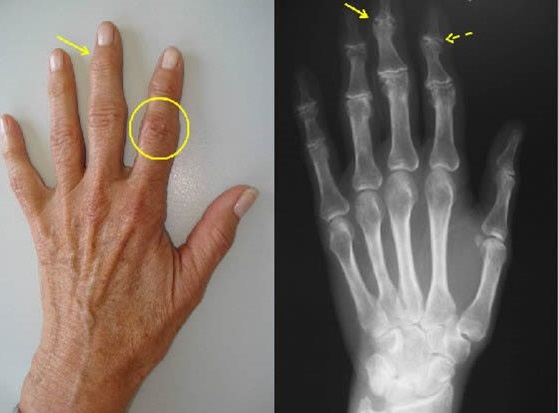

Los nódulos (o protuberancias) que aparecen en las articulaciones de los dedos de las manos son una patología ocasionada principalmente por el desgaste de las articulaciones. Los traumatismos y enfermedades de depósito también pueden ocasionar nódulos, pero en menor frecuencia.

La erosión o daño del cartílago articular produce una artropatia degenerativa que va modificando el hueso subcondral, por ello las modificacones de longitud y ángulo de inclinación del hueso, pueden ocasionar desviación de las articulaciones (observando los "dedos torcidos"). El daño del cartílago y hueso subcondral produce inflamación de la articulación lo que genera dolor, limitación de los movimientos (sensación de rigidez), sensibilidad aumentada.

El diagnóstico de los nódulos de los dedos es principalmente clínico. La inspección visual, la palpación y la verificación de los arcos de movilidad de la articulación afectada generalmente son suficientes para hacer el diagnóstico.

Se puede solicitar una Rx, donde se puede evidenciar daño de la articulación, formación de osteofitos, disminución del espacio articular o luxaxión de las falanges. Estos cambios se conocen como artropatía y ayudan a identificar que tan avanzado está el problema y saber el tratamiento apropiado.